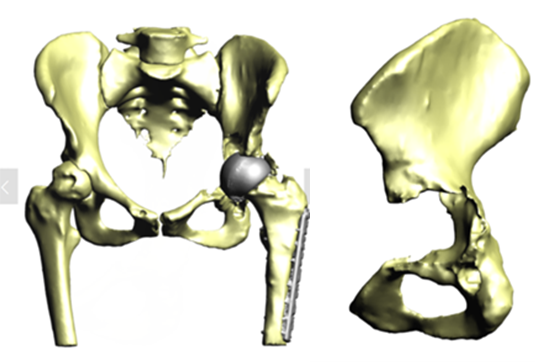

The patient, a 49-year-old woman, underwent metal-on-metal (MoM) hip resurfacing procedure in 2001 due to a unilateral hip dysplasia (DDH). 17 years later, she presented with mild hip pain but extensive loss of bone in the pelvis which was presumably caused by an inflammatory reaction to metal wear debris. Her blood metal ion levels were 100 times higher (cobalt 188 bbp and chromium 126 bbp) than from patients with well-functioning MoM hips.

The case posed multiple challenges. The patient was at imminent risk of pelvic fracture without surgery. However, surgery itself also risked fracture of the pelvis during implant removal. Furthermore, the remaining pelvic bone was poisoned by metal debris and thus the patient’s bone integrity was compromised, which could affect the stability of a new implant.

A multidisciplinary team decided that revision surgery was necessary due to the risk of fracture and very high metal ion levels. The plan involved removing the existing MoM implant and fitting a custom 3D-printed acetabular cup. The procedure required meticulous care to avoid causing fractures during implant removal. The new cup would only be effective if the pelvis remained intact.

The operation was successful, with minimal bone loss during implant removal. A custom-made titanium acetabular cup was fitted and stabilized with screws. Postoperative imaging confirmed correct implant positioning and satisfactory fixation. The patient’s recovery was positive, with significant reductions in metal ion levels and the restoration of pain-free hip function.

This case represents ALTR with MoM, which was characterized by extensive osteolysis of pelvic bone, which was presumably caused by metal wear debris. Elevated blood levels of chromium and cobalt further supported this hypothesis.

This case demonstrates the importance of precise surgical planning and execution in complex hip revision surgeries. The use of 3D-printed implants tailored to the patient's anatomy greatly improved the chances of successful fixation despite significant bone loss. Update at 6 years post operative is that the patient living a full and active life with excellent hip function. More details about this type of surgery has been published by Professor Hart: